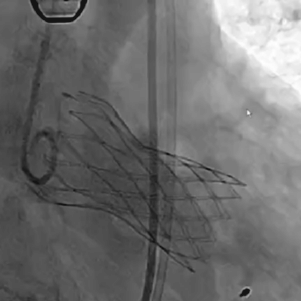

从三叶瓣重度钙化到二叶瓣畸形的根部解剖,从单纯主动脉瓣反流到入路极端迂曲挑战的案例。TaurusOne凭借其优异的柔顺性,支撑力强及内外层双侧裙边的特点,都能从容应对复杂的临床患者解剖结构。从患者的临床选择到术后的长久获益,从手术入路的种类到术中操作的注意事项,从围术期卒中的循证医学到术后的抗凝抗栓用药规范,在线专家共同交流彼此中心的围术期TAVR经验和分享现阶段经导管主动脉瓣置换的诊疗策略。针对当前TAVR领域多个热点学术问题进行了热烈的讨论,现场可谓精彩纷呈、高潮迭起。专家们纷纷借此契机相互交流探讨,分享各自的单中心经验,力求进一步提升TAVR手术的安全性和有效性,为主动脉瓣相关疾病的患者带来长远综合获益。